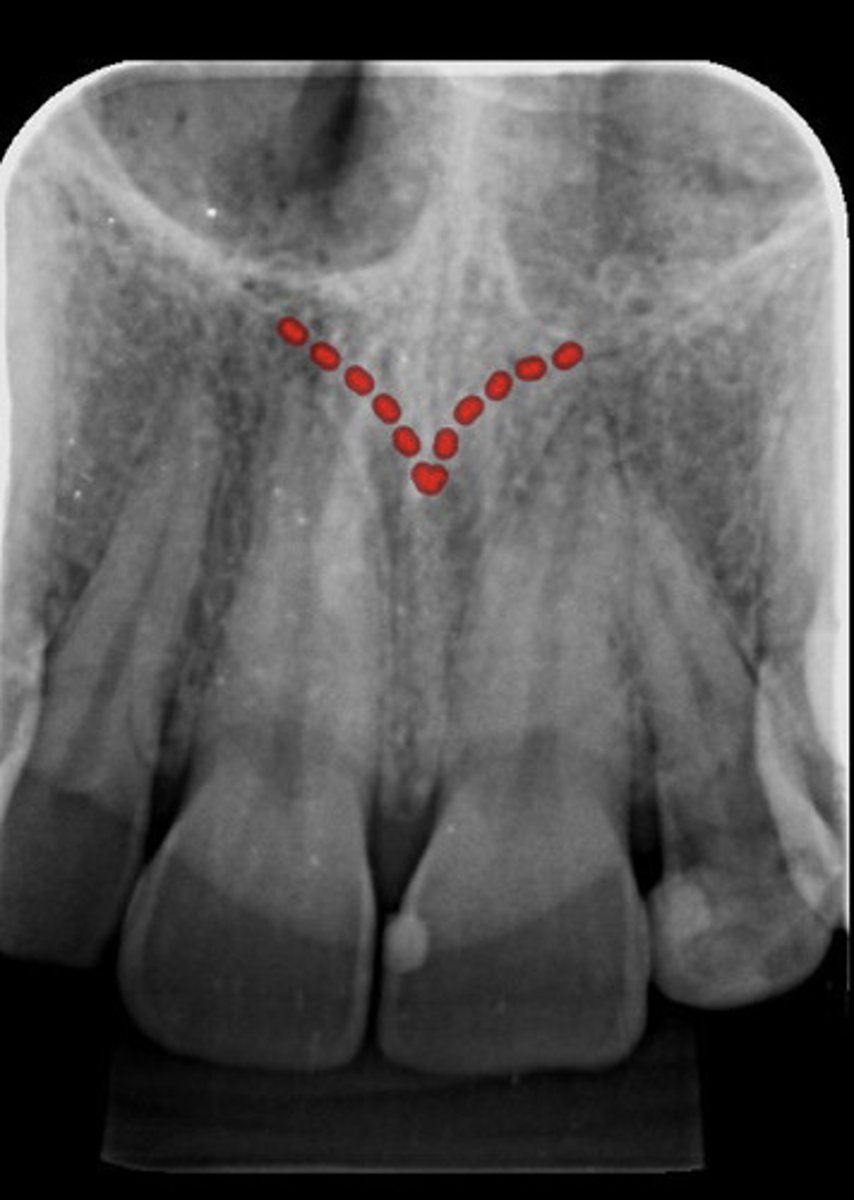

Incisive foramen

What are the red dotted lines representing?